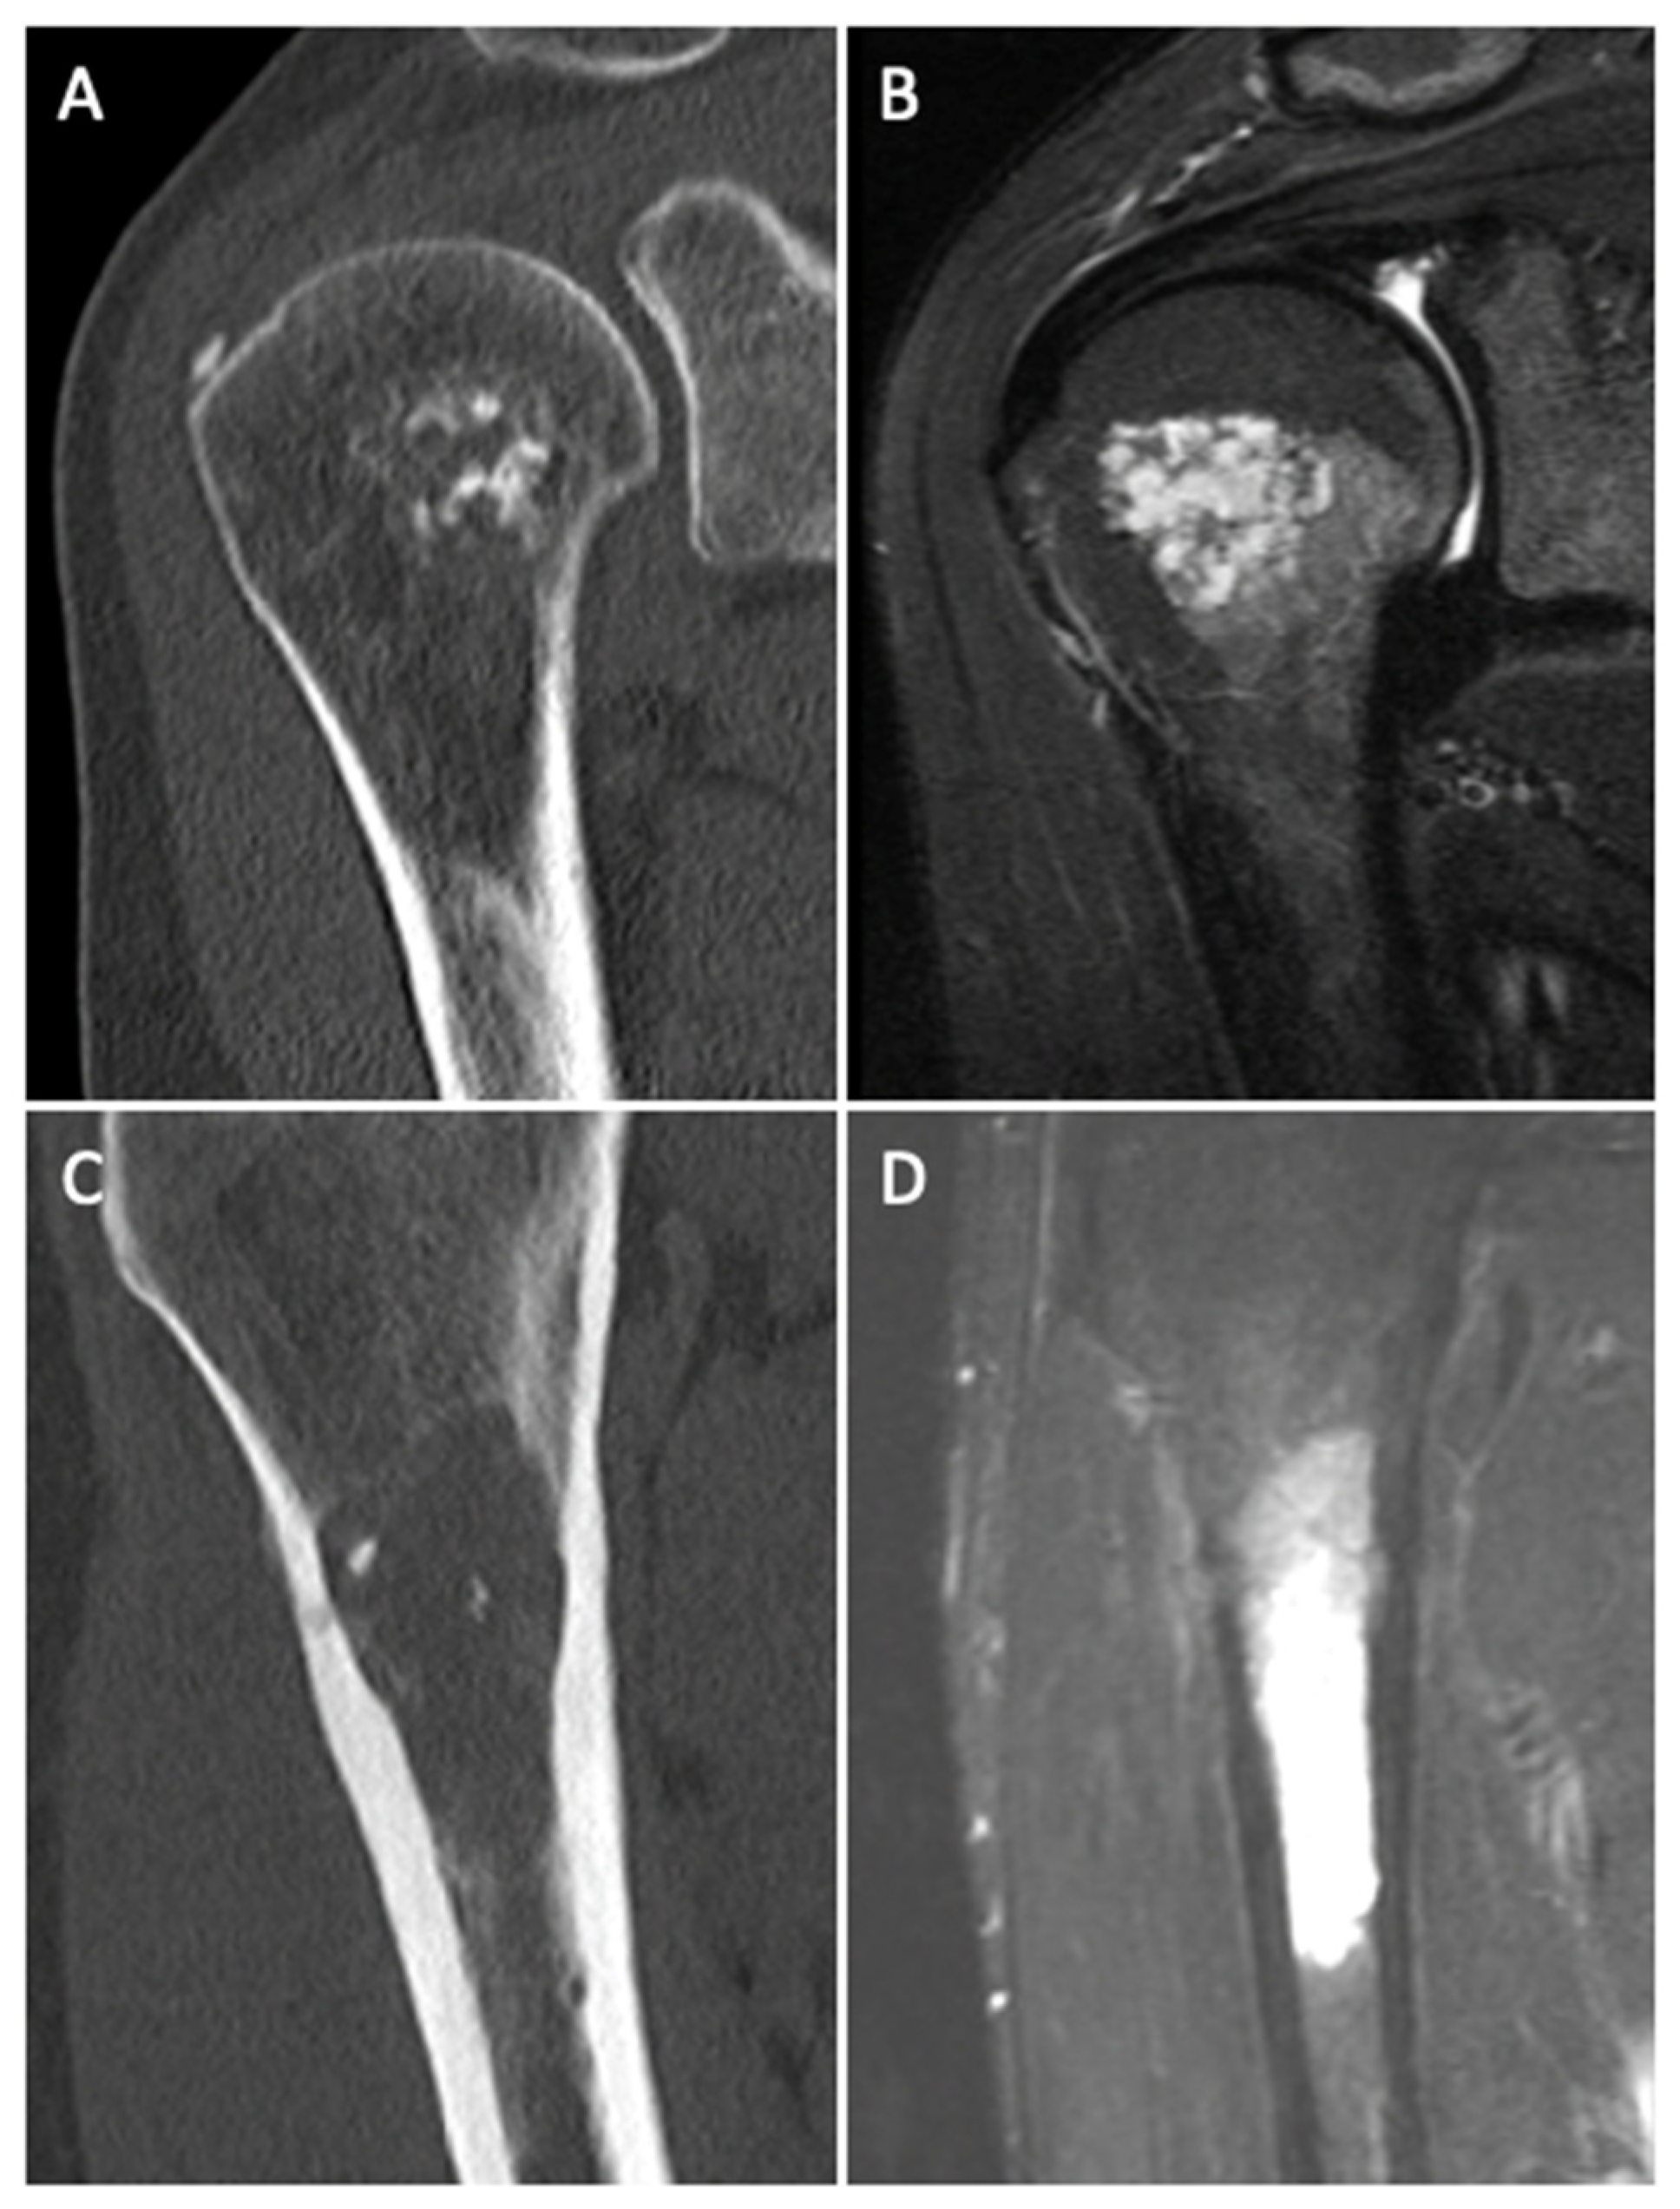

Differentiating Enchondromas and Atypical Cartilaginous Tumors in Long Bones with Computed Tomography and Magnetic Resonance Imaging

3.4. CT and MR Imaging Criteria